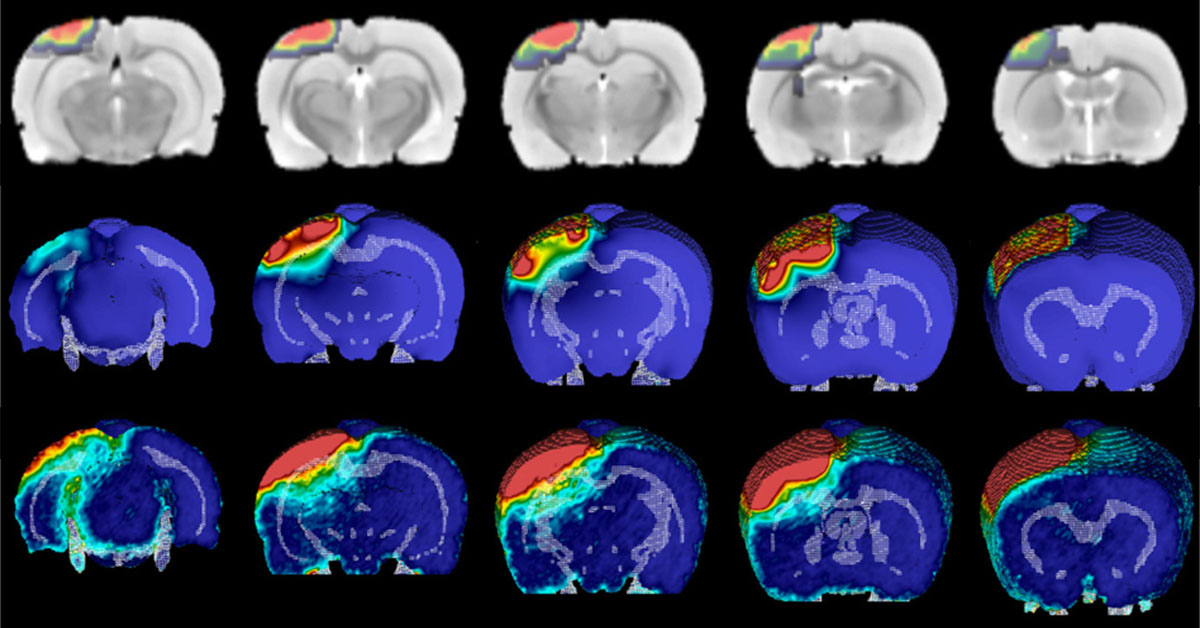

Οι ερευνητές του Πανεπιστημίου της Κοπεγχάγης, με επικεφαλής τον καθηγητή Δημήτρη Στάμου του Τμήματος Χημείας και βασικό συνεργάτη του τον δρα Ελευθέριο Κοσμίδη, βρήκαν για πρώτη φορά ότι ένα ζωτικό ένζυμο, το οποίο επιτρέπει τη μεταβίβαση των σημάτων μέσα στον εγκέφαλο, δεν λειτουργεί σε συνεχή βάση (όπως είχε θεωρηθεί αυτονόητο μέχρι σήμερα), αλλά «ανοιγοκλείνει» με τυχαίο τρόπο και μάλιστα κάνει διαλείμματα ακόμη και ολόκληρων ωρών, χωρίς όμως αυτό να οδηγεί τον εγκέφαλο να «κατεβάσει ρολά», όπως θα αναμενόταν.

Εκατομμύρια εγκεφαλικοί νευρώνες στέλνουν συνεχώς μηνύματα μεταξύ τους, κάτι που τροφοδοτεί τη σκέψη, τη μνήμη, την κίνηση του σώματος και άλλες λειτουργίες.

Όταν 2 νευρώνες ανταλλάσουν ένα μήνυμα, ουσίες που λέγονται νευροδιαβιβαστές μεταφέρονται από τον έναν νευρώνα στον άλλον με τη βοήθεια ενός ζωτικού ενζύμου που παρέχει την απαραίτητη ενέργεια, έτσι ώστε να είναι εφικτή η μεταβίβαση.

Έως τώρα, σε όλον τον κόσμο οι επιστήμονες πίστευαν ότι αυτά τα -απολύτως αναγκαία για την επιβίωση ενός οργανισμού- ένζυμα είναι ενεργά μονίμως, αλλά όπως αποκάλυψε η νέα έρευνα μόνο αυτό δεν συμβαίνει.

Η στενή παρακολούθηση του ενζύμου V–ATPase από τον δρα Στάμου και την ομάδα του έφερε στο φως την περιοδική και διαλείπουσα δράση του ενζύμου.

Αντίθετα με τη διαδεδομένη άποψη και αντίθετα από πολλές άλλες πρωτεΐνες, αυτά τα ένζυμα μπορεί να σταματούν να δουλεύουν για αρκετά λεπτά ή και για ώρες.

Παρόλα αυτά, οι εγκέφαλοι των ανθρώπων και των άλλων θηλαστικών παραμένουν με θαυματουργό τρόπο ικανοί να λειτουργούν».

Ο δρ Στάμου, ο οποίος είναι απόφοιτος του βρετανικού Πανεπιστημίου του Λιντς και της Ελβετικής Ομοσπονδιακής Πολυτεχνικής Σχολής της Λωζάννης (EPFL), χαρακτήρισε «σχεδόν ακατανόητο» ότι στη διάρκεια αυτής της άκρως κρίσιμης διαδικασίας μεταφοράς των νευροδιαβιβαστών μεταξύ των νευρώνων «βρίσκουμε ότι στο 40% του χρόνου αυτά τα μόρια των εν λόγω ενζύμων είναι απενεργοποιημένα».